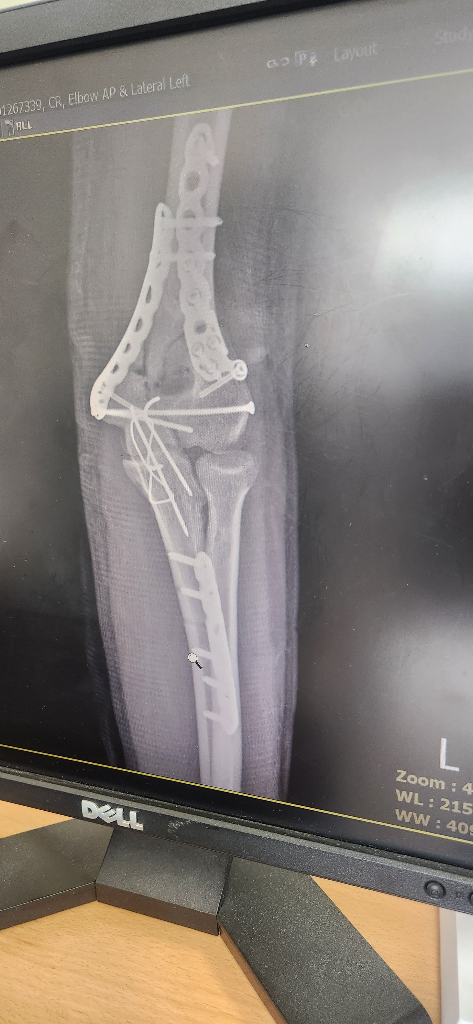

제가 골절에 신경마비가 있는데 신검 몇급 나올까요?

제가 1월에 다쳐서 사완골 골절에 척골골절 그리고 척골신경 마비가 있어요

그런데 저번 신검 1급을 받고 이번에 이걸로 재신검을 요청 했습니다.

팔각도 좀 모자라가 펴지고 척골신경 신호가 없다고 확인됩니다. 몇급을 받을까요?